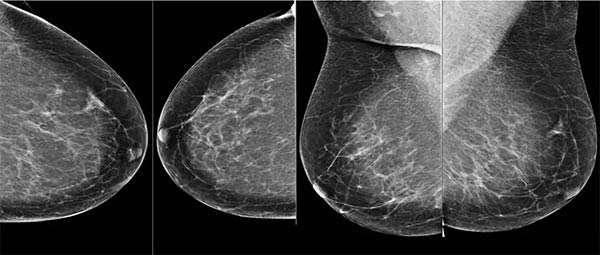

L’ingresso di DeepMind nel team Google Health ufficializzato nei mesi scorsi inizia a dare i frutti sperati. Dalla squadra di Alphabet al lavoro su intelligenza artificiale e machine learning l’annuncio di un progetto destinato all’ambito medico: un algoritmo in grado di affiancare medici e personale specializzato nell’analisi delle immagini ottenute mediante l’esame della mammografia.

Il progetto messo in campo ha come obiettivo quello di ridurre il numero di falsi positivi e di falsi negativi, incrementando così l’accuratezza dei referti, evitando che le pazienti possano essere sottoposte a trattamenti per cancro al seno o altre patologie che interessano l’organo quando non necessarie. Al tempo stesso, stando ai risultati emersi dai primi test, l’IA sembra in grado di identificare con precisione le porzioni delle radiografie nelle quali potrebbero nascondersi cellule tumorali, anche se difficilmente riconoscibili da un occhio esperto.

DeepMind ha messo alla prova l’algoritmo sulle immagini di pazienti provenienti da USA e UK, ovviamente fornite in forma anonima. Prendendo in considerazione gli Stati Uniti, i falsi positivi sono risultati inferiori del 5,7% e i falsi negativi del 9,4% rispetto a quanto avvenuto sottoponendo gli esiti delle stesse mammografie ai medici. Curiosamente, sono emerse percentuali più basse in relazione al Regno Unito: questo indicherebbe una minore accuratezza nella lettura degli esami oltreoceano.